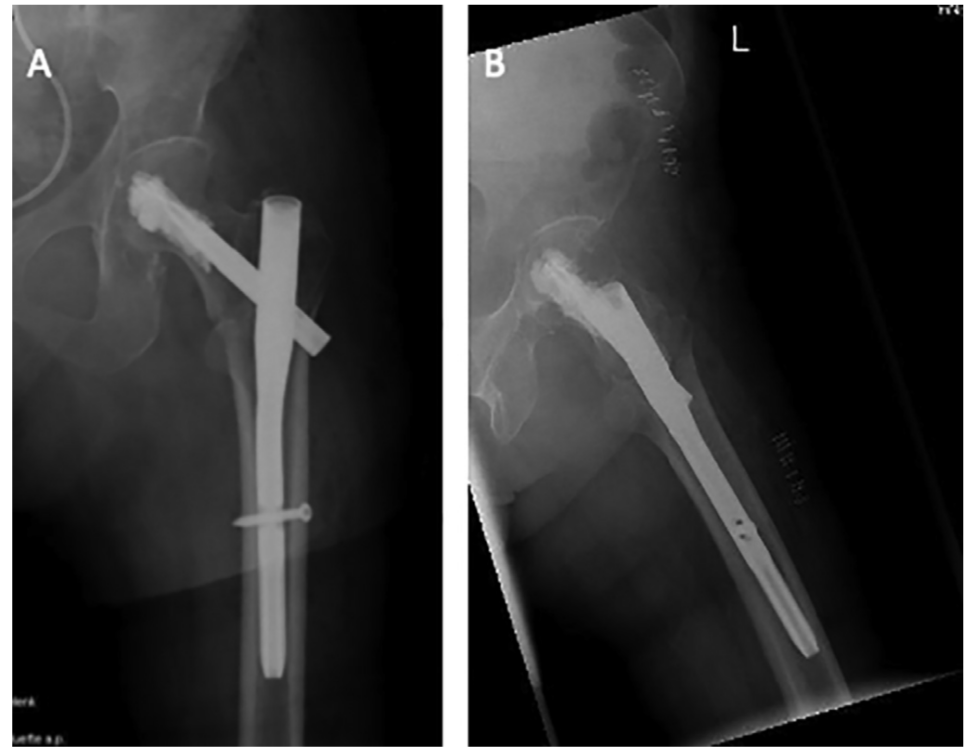

粗隆间骨折好发于老龄患者,为三大骨质疏松性骨折之一,通常需采用内固定治疗。粗隆间骨折内固定的选择,与骨折类型密切相关。关于小转子及内侧壁的重要性,已经越来越受到重视,部分内固定的失效也与其相关。有学者研究了粗隆间骨折累及小转子及内侧壁的大小与内固定失效的关系,结果发表在Injury期刊上。